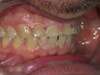

Nous avons reçu notre patient qui souffre de bruxisme intense et s'est errodé 3/4 mn de son étage inférieur.

Nous avons surélevé son occlusion par des onlays postérieurs pour dégager de l'espace antérieur et 6 couronnes antérieures ont été posées. Nous en avons éclairci la teinte globale des dents